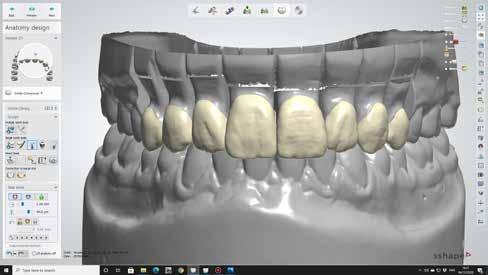

A minta beolvasása után számítógéppel terveztük meg a híd vázát (7. kép). 0,06 mm-es cementrést terveztünk a teljes karfelület alá, 1 mmre végződve a preparáció szélétől (8–11. képek)